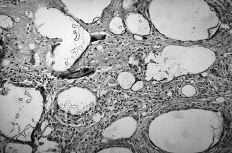

ABFigura 3. Aspecto microscópico. A: Sinovitis hipertrófica con granulomas por silicona (HE, 40*). B: Reacción de células gigantes a cuerpo extraño (HE, 250*).

Debido a esta falta del implante hemos observado en un 20% de los casos luxación y subluxación de la artroplastia, en un 30% inestabilidad en DISI y en un 10% en VISI. La incidencia de imágenes líticas intraóseas y sinovitis por liberación de partículas de silicona en nuestra serie es del 40%. Surgen por la abrasión y el desgaste del implante y producen una sinovitis hipertrófica con granulomas por silicona.19 Microscópicamente se aprecia la respuesta del huésped a estas partículas como una reacción de células gigantes a cuerpo extraño. Los leucocitos y macrófagos fagocitan el material, pero la silicona no se afecta por las enzimas lisosomales, lo que induce una sinovitis reactiva que no es exclusiva de la silicona (PMMA, polietileno y otros materiales metálicos), estando siempre en relación con el tamaño de la partícula. Las partículas de silicona son de 30 a 60 micras de diámetro. Estos implantes se han desaconsejado para la sustitución del escafoides y del semilunar, ya que al estar sometidos a importantes cargas de compresión se produce su fragmentación.31 Los factores que desgastan el implante de silicona y contribuyen a la formación de partículas son las fuerzas excesivas a través del implante debidas a la asociación de inestabilidad o de colapso, una malposición o exceso de tamaño, exceso de movilidad y abuso de la actividad diaria.43,44